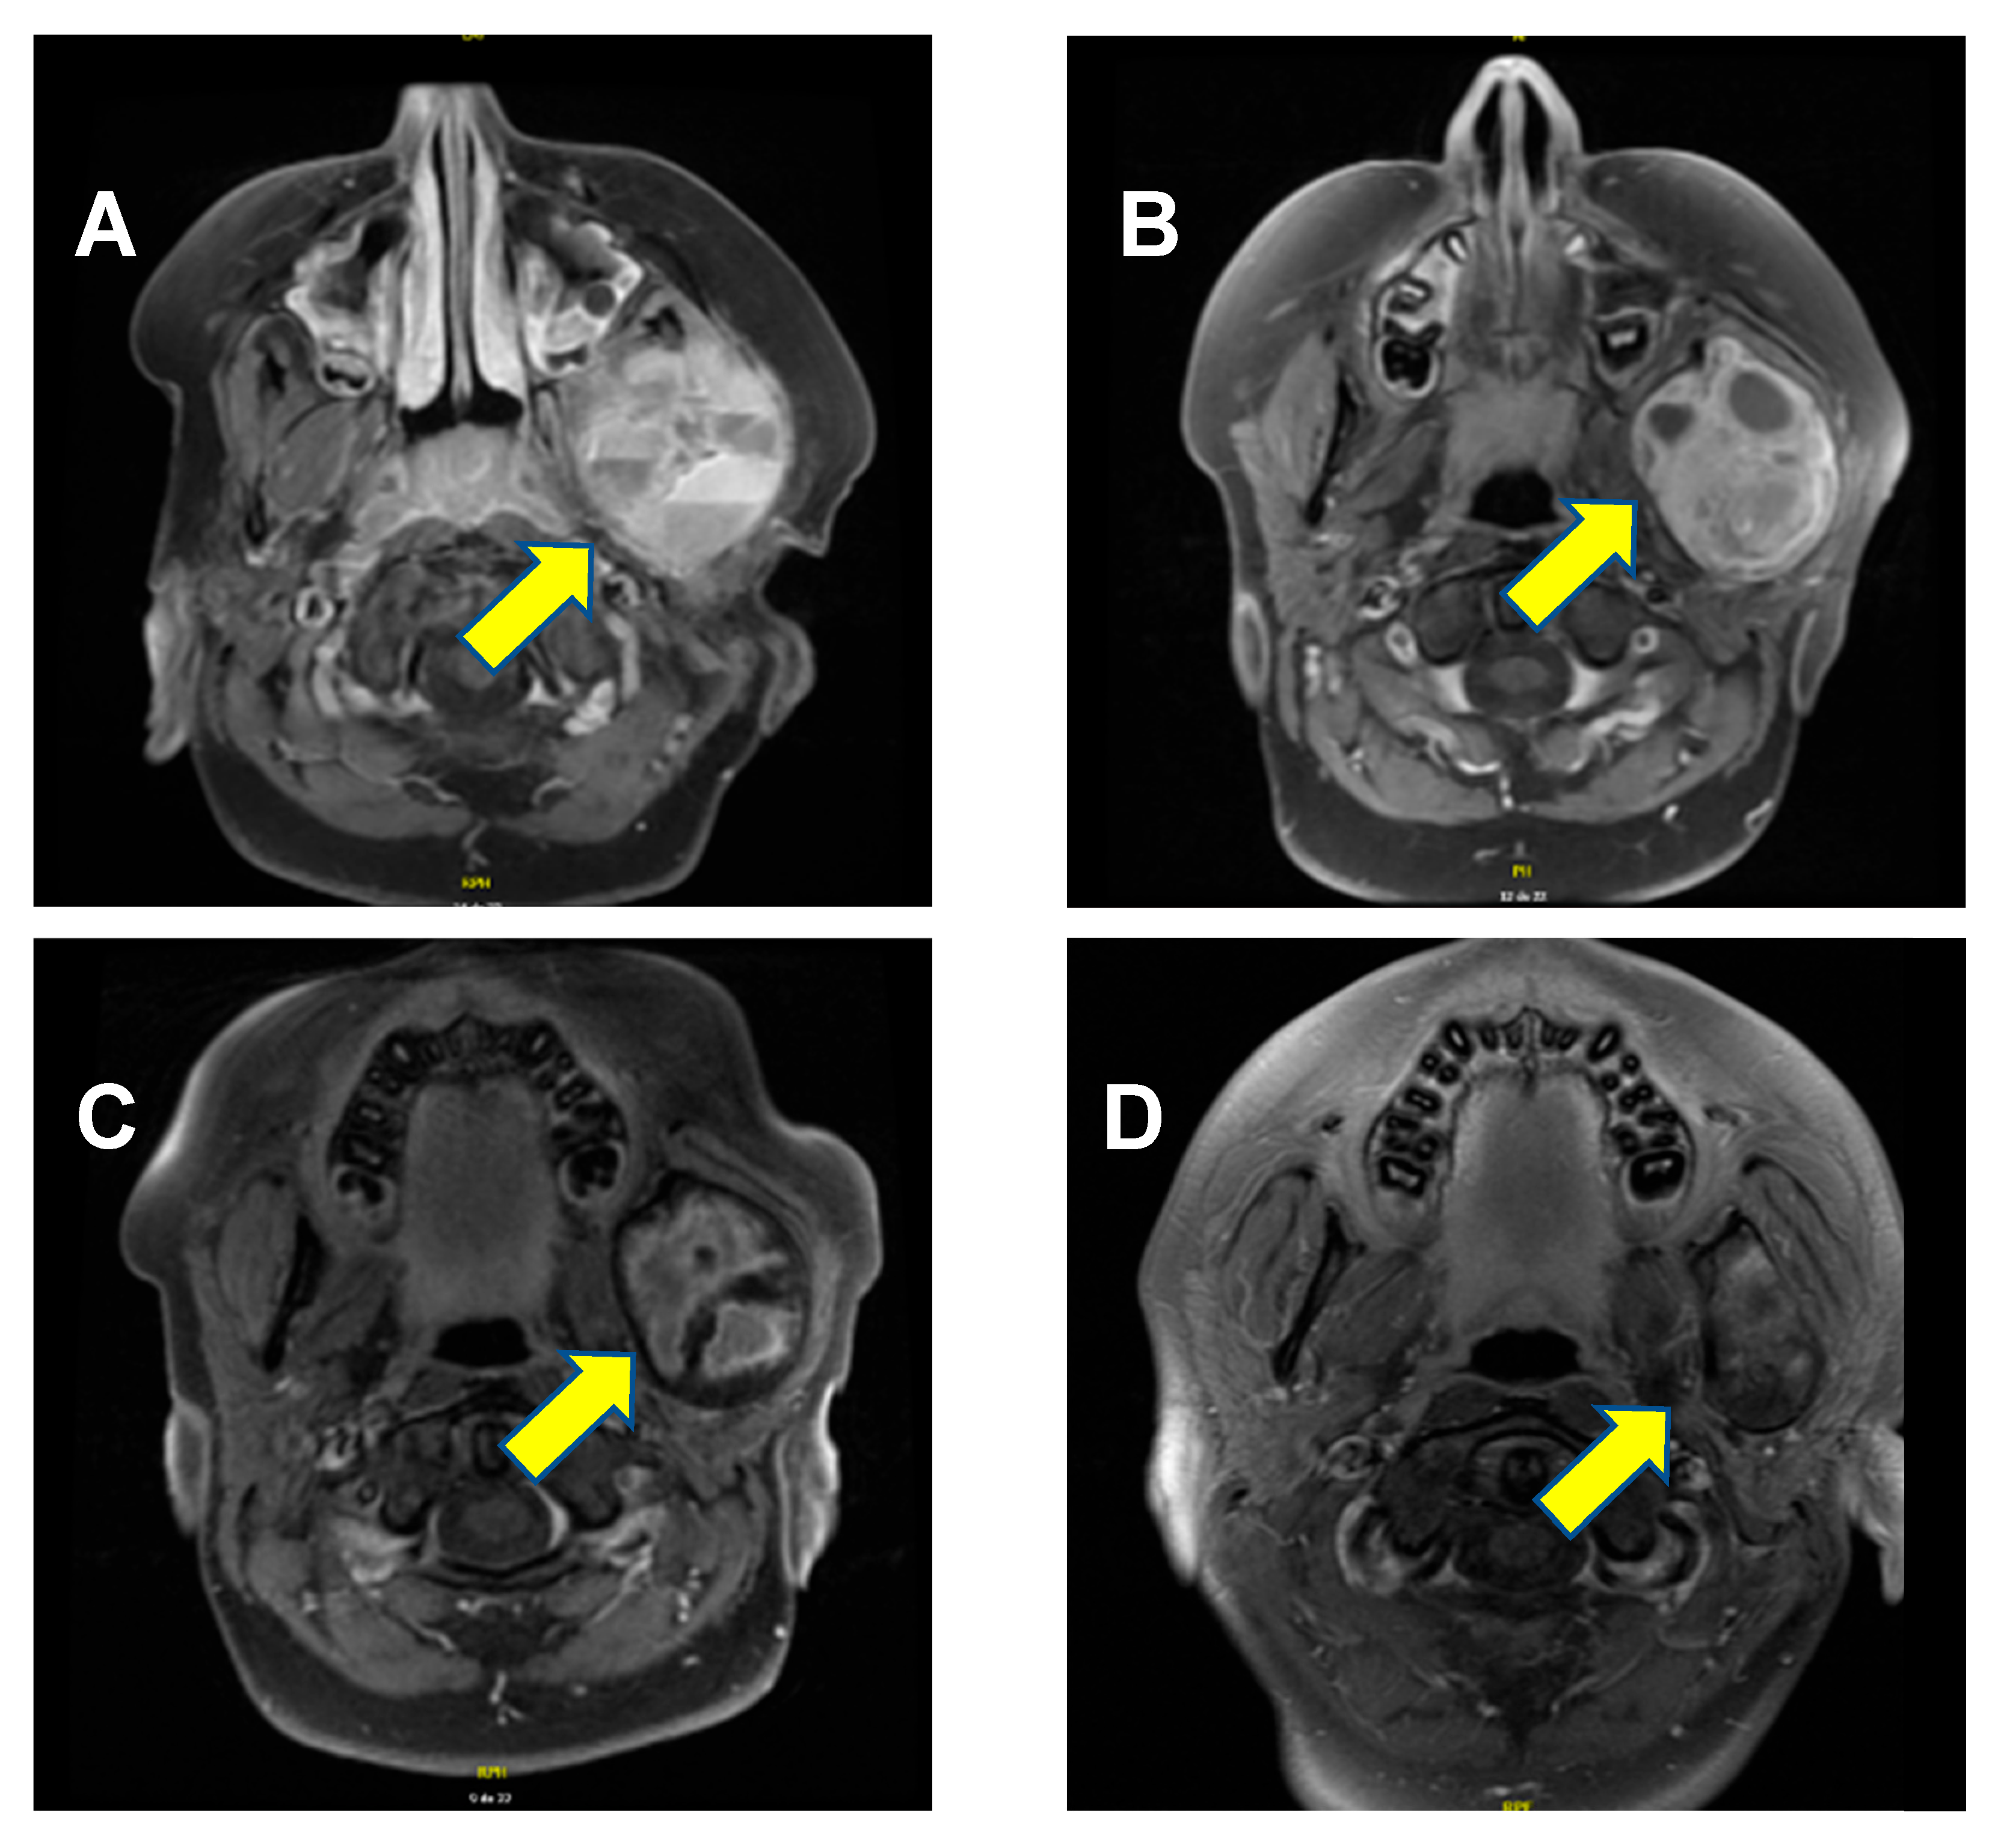

Remarkably, the lesion continued to shrink even after denosumab discontinuation. At the most recent follow-up MRI, performed 26 months after treatment discontinuation, the lesion measured 4.3 cm × 2.6 cm × 3.5 cm, (Figure 1D). Most importantly, the significantly deformed malformation on the left aspect of the mandible is clinically no longer apparent; the aneurysmal bone cyst is meanwhile just barely palpable, and the patient no longer complains of any pain. A timeline of the patient’s clinical course, from initial discovery to lesion regression and symptom resolution, is provided in Figure 2.

Figure 2. Timeline of patient’s clinical course from discovery of mass to regression of lesion and symptoms’ resolution.